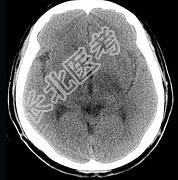

- 单项选择题男,57岁, 头痛、头晕1周,言语不清, 饮水呛咳两天,既往有鼻咽癌病史, 给予放射治疗,CT检查如图所示, 最可能的诊断是 ( )

A、放射性脑病

B、脑梗死

C、脱髓鞘病变

D、胶质瘤

E、脑炎